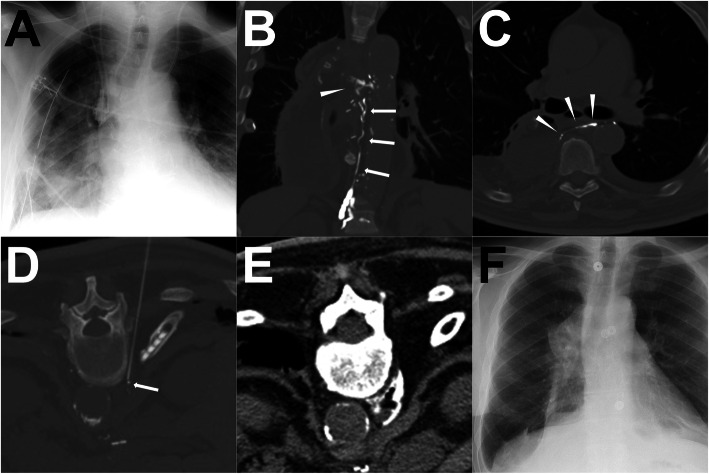

Fig. 7.

A patient underwent ALVS procedure after post-LAG CT. Note: After the surgery, the right chylothorax appeared with hyperdensity of the right lower lung in the chest radiogram (a). The coronal MIP images of post-LAG CT demonstrated a definite rupture (white arrowhead) of the thoracic duct (white arrows) and the extravasation to the right pleural cavity (b). The axial MIP image demonstrated a clear rupture of the thoracic duct (c). The lower thoracic duct was regarded as the target afferent LV for the ALVS and a 21-G Chiba needle was used to puncture close to the lower thoracic duct (d). Afterwards, 1 ml contrast followed with 4.0 ml 95% Ethanol being injected. The post-ALVS CT scan showed an ideal distribution of the sclerosant around the target thoracic duct (e). Eleven (11) days after ALVS, the chest radiogram shows no obvious recurrence of the chylothorax (f). Abbreviations: ALVS – afferent lymphatic vessel sclerotherapy; post-LAG CT – post-lymphangiographic computed tomography; MIP – maximum intensity projection; LV – lymphatic vessel